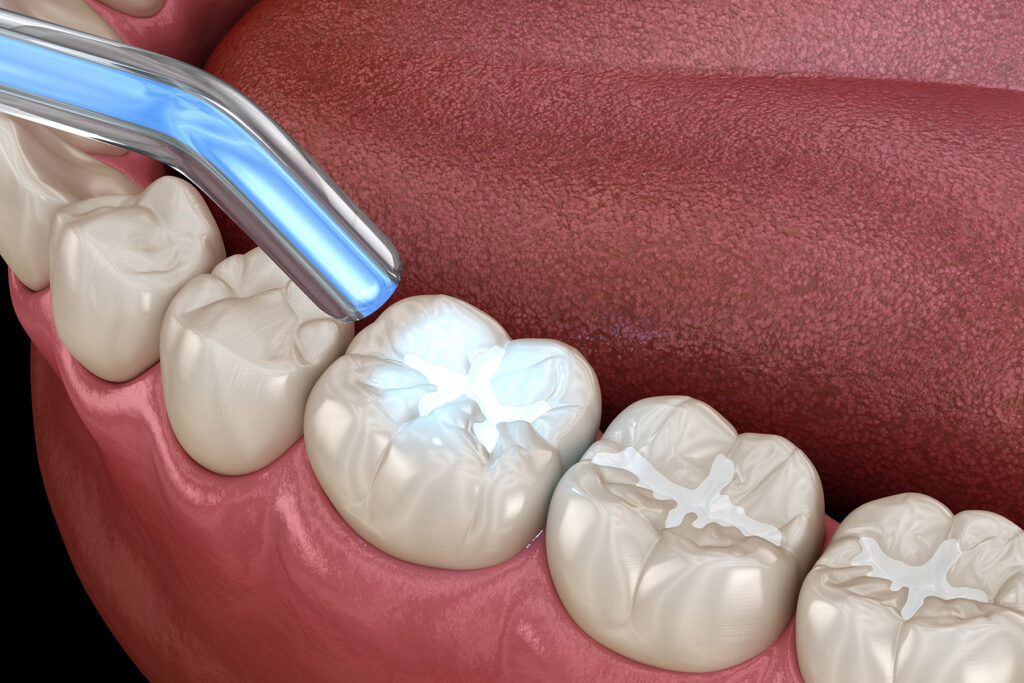

Transform your smile with our innovative digital implants, offering speed, precision, and a non-invasive approach for a truly comfortable dental experience.